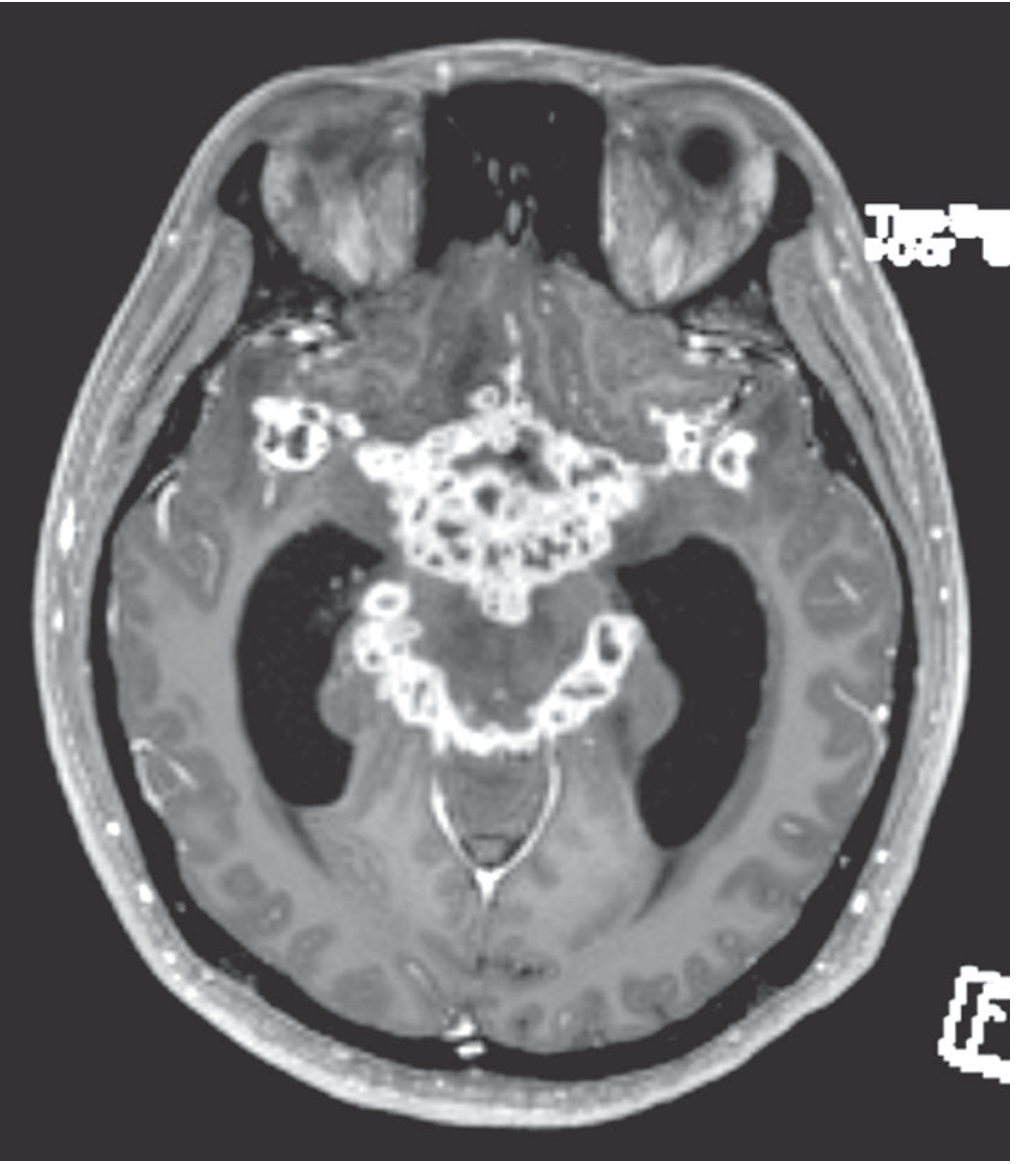

MRI in tuberculous meningitis showing gadolinium enhancement of the basal meninges, reflecting multiple abscesses, accompanied by hydrocephalus and cranial nerve palsies

Figure: MRI in TB meningitis — gadolinium enhancement of basal meninges, hydrocephalus, and cranial nerve palsies (Adams & Victor)

• CT/MRI: Gadolinium enhancement of basal meninges is characteristic

• Hydrocephalus

• Deep cerebral infarctions (basal ganglia, internal capsule) from vasculitis of circle of Willis branches

• Tuberculomas: enhancing ring lesions (2–12 mm), may be multiple